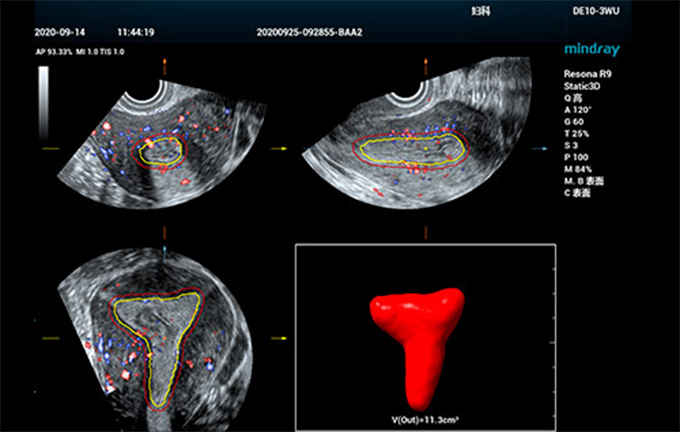

Effici?nte kwantificatie voor endometrium

In de afgelopen jaren zijn de onvruchtbaarheidscijfers bij vrouwen toegenomen en lopen vrouwen een verhoogd risico op ziekten van het voortplantingssysteem en tumoren als gevolg van veranderingen in levensstijl, milieuvervuiling en lichamelijke aandoeningen. De rol van echografie bij het gynaecologisch onderzoek is onvervangbaar, vooral bij preconceptie-scenario's. Regelmatige echo-onderzoeken zijn echter vervelend en tijdrovend, en berusten in hoge mate op handmatige aanpassingen.

Smart ERA

Om de effici?ntie en nauwkeurigheid van gynaecologische echodiagnostiek te verbeteren en een vroege diagnose van reproductieve aandoeningen en tumoren toegankelijker te maken, heeft Mindray een reeks slimme oplossingen ontwikkeld om artsen te helpen een effici?nte klinische diagnose te stellen voor folliculaire en uteriene echografische onderzoeken. Inspelend op de behoeften aan endometriumreceptiviteitsonderzoek, maakt Smart ERA, het eerste volledig geautomatiseerde instrument voor endometriumreceptiviteitsanalyse dat door ons is ontwikkeld, automatische 3D-beeldvorming van het endometrium mogelijk, zelfs voor verschillende soorten structuren. Het ondersteunt de automatische meting van het volume en de dikte van het endometrium, evenals de endometriale bloedstroomindex. Het gestroomlijnde werkproces verbetert de consistentie van het onderzoek en de diagnostische effici?ntie aanzienlijk, waardoor echografisten met meer vertrouwen en gemak pre-zwangerschapsonderzoeken kunnen uitvoeren.